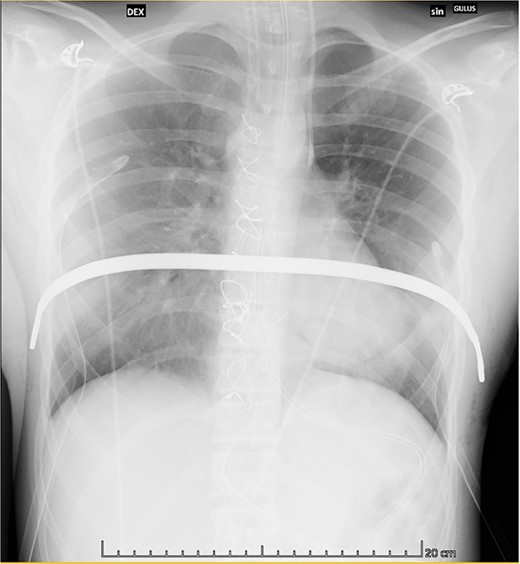

Ten months after surgery, the patient is asymptomatic with a noticeable PE correction (Fig. 2). Bar removal is planned 3 years after primary repair in a cardiothoracic surgical setting.

Postoperative chest X-ray showing the correct positioning of the bar.